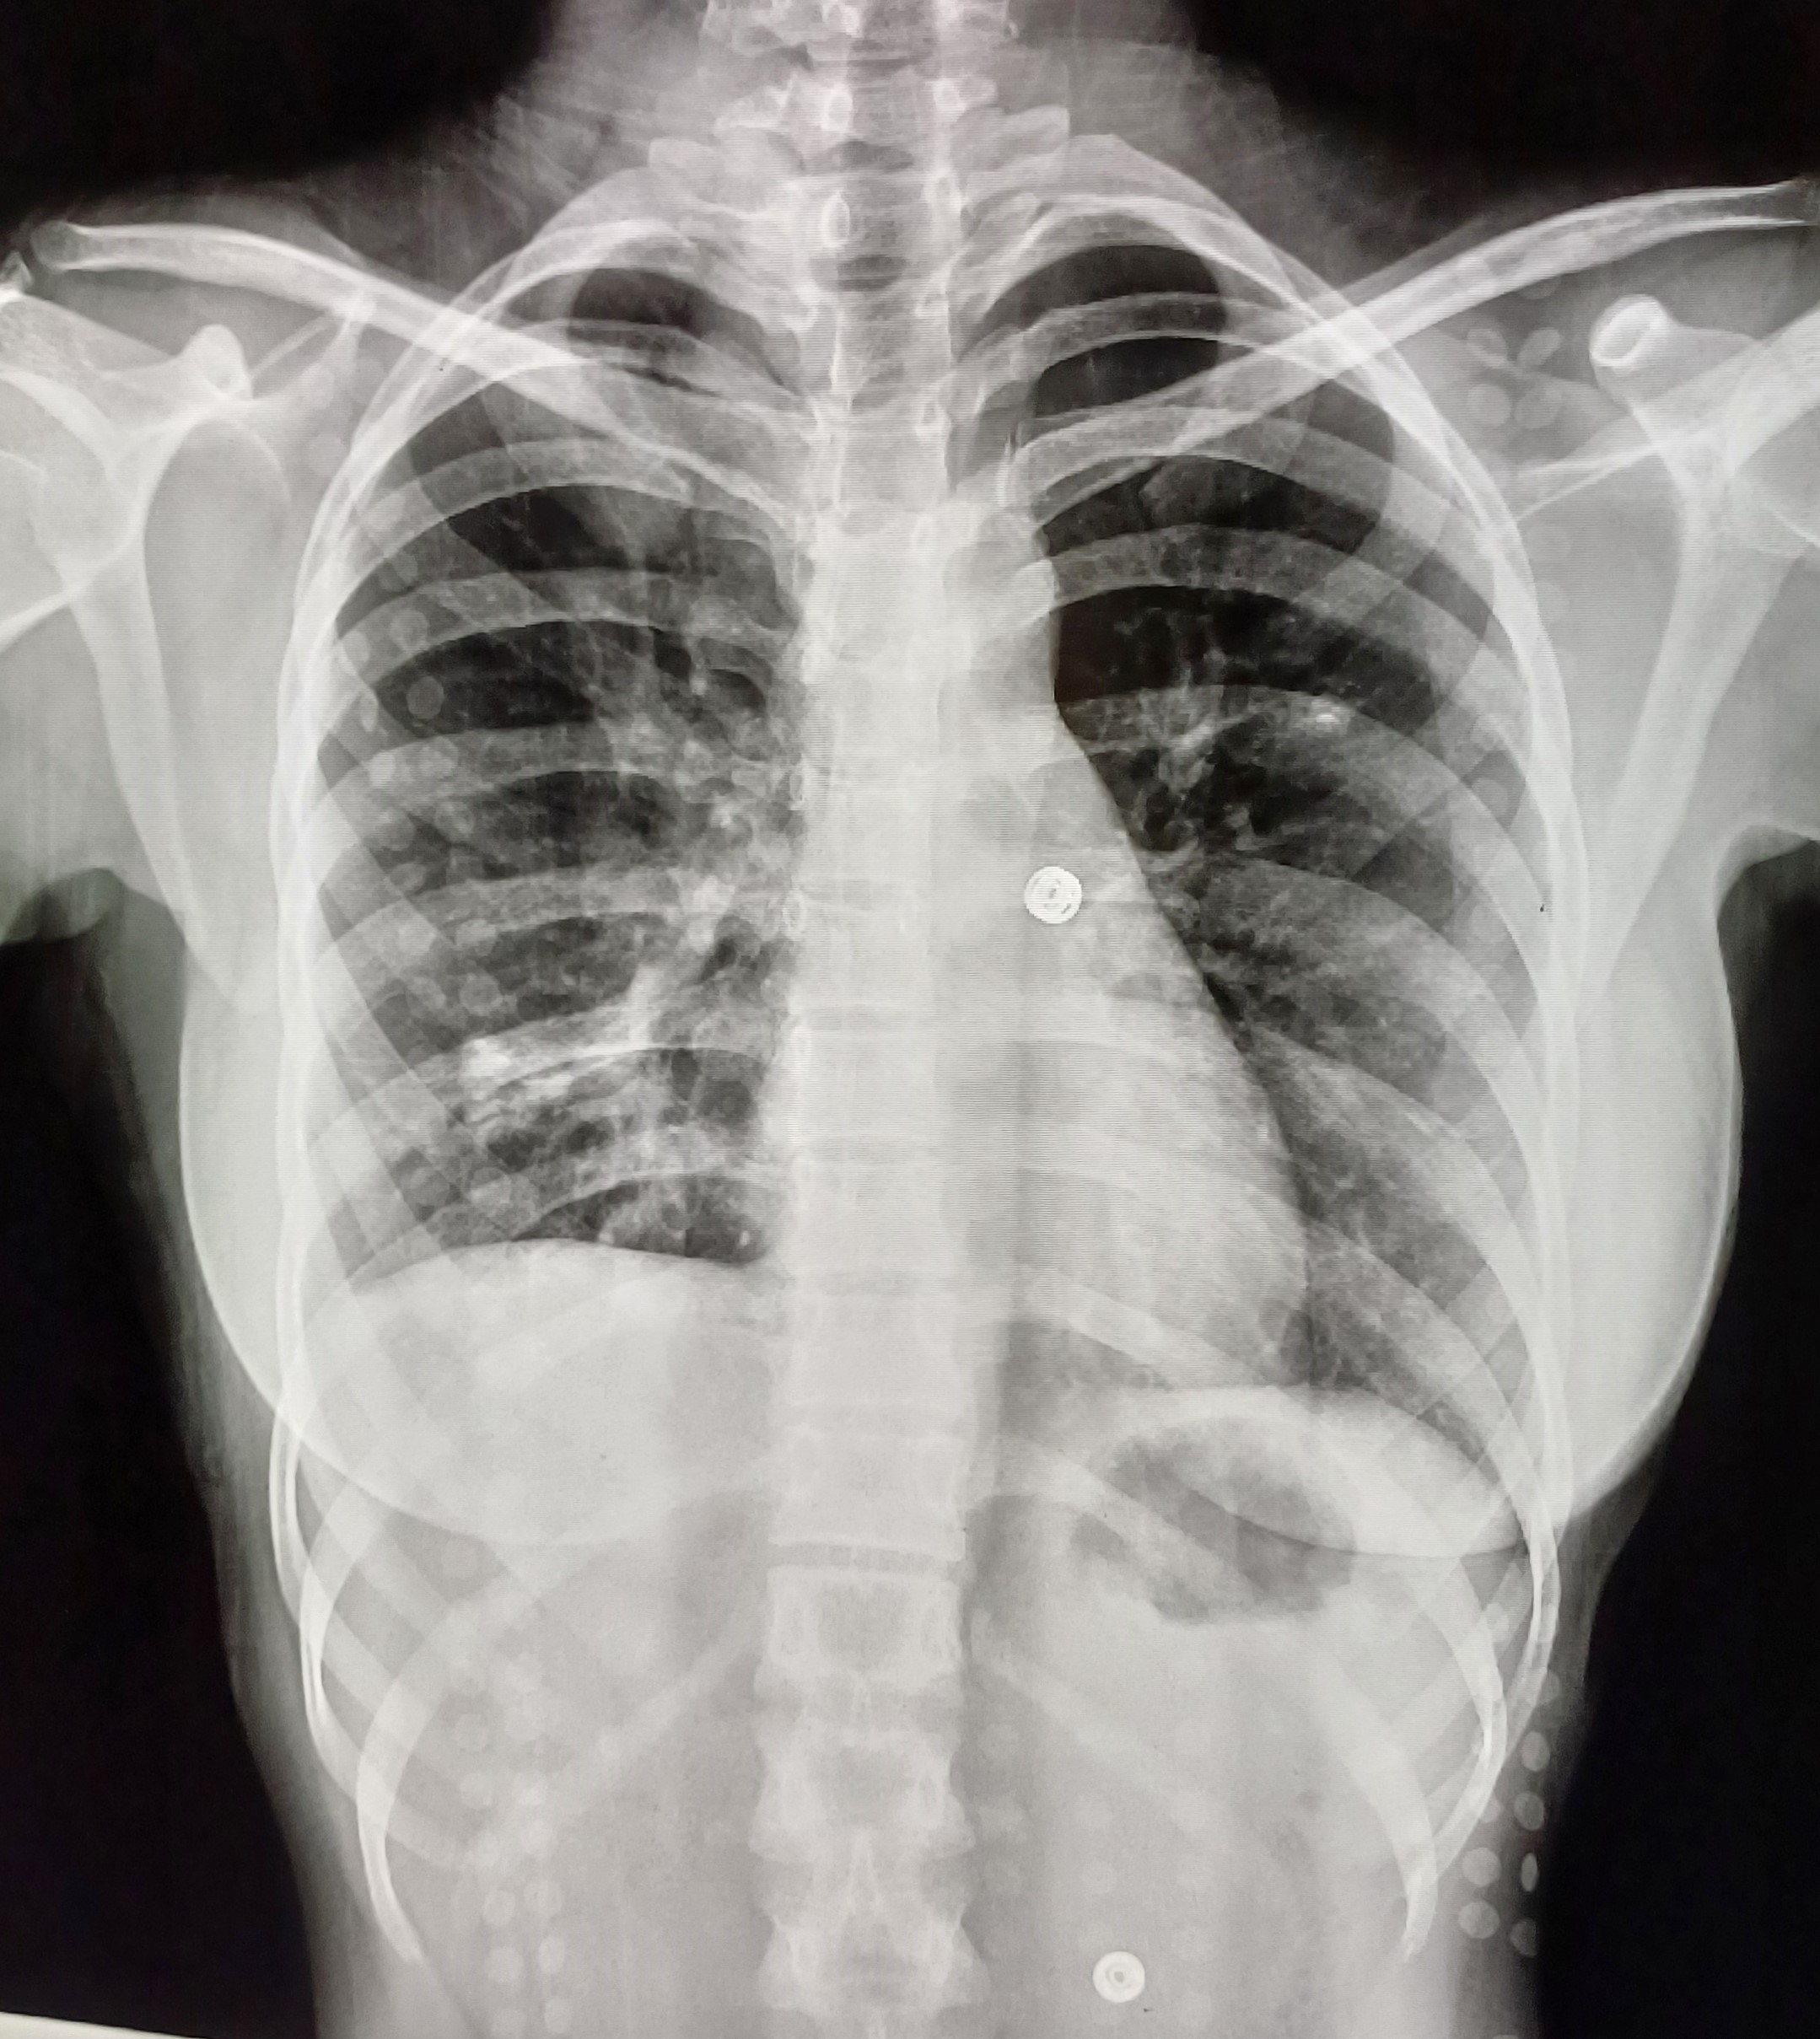

| 5 | IGGMC, Nagpur, Nagpur | P2 | 29-4467 | Meera Gohare | Consent taken on Paper | 64 Yrs. |

Provisional Diag : ?

Final Diag : Disseminated TB (Miliary TB With Abdomen Koch) |

TB Case (Confirmed) | Abnormality visible on x-ray |